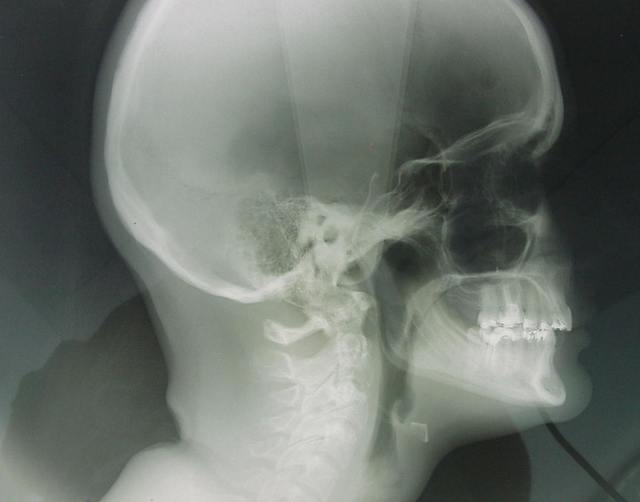

chir d'avancée mand et max

voici les radios de ma chir, j'aurais les photos lundi pour ceux que ça intéresse.